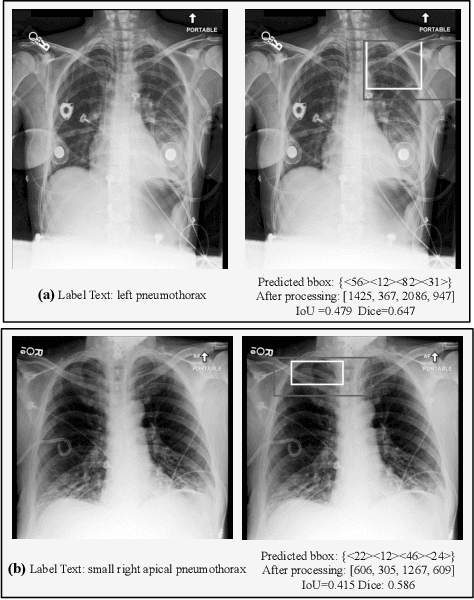

Multimodal Large Language Models (MLLMs) inherit the superior text understanding capabilities of LLMs and extend these capabilities to multimodal scenarios. These models achieve excellent results in the general domain of multimodal tasks. However, in the medical domain, the substantial training costs and the requirement for extensive medical data pose challenges to the development of medical MLLMs. Furthermore, due to the free-text form of answers, tasks such as visual grounding that need to produce output in a prescribed form become difficult for MLLMs. So far, there have been no medical MLLMs works in medical visual grounding area. For the medical vision grounding task, which involves identifying locations in medical images based on short text descriptions, we propose Parameter-efficient Fine-tuning medical multimodal large language models for Medcial Visual Grounding (PFMVG). To validate the performance of the model, we evaluate it on a public benchmark dataset for medical visual grounding, where it achieves competitive results, and significantly outperforming GPT-4v. Our code will be open sourced after peer review.